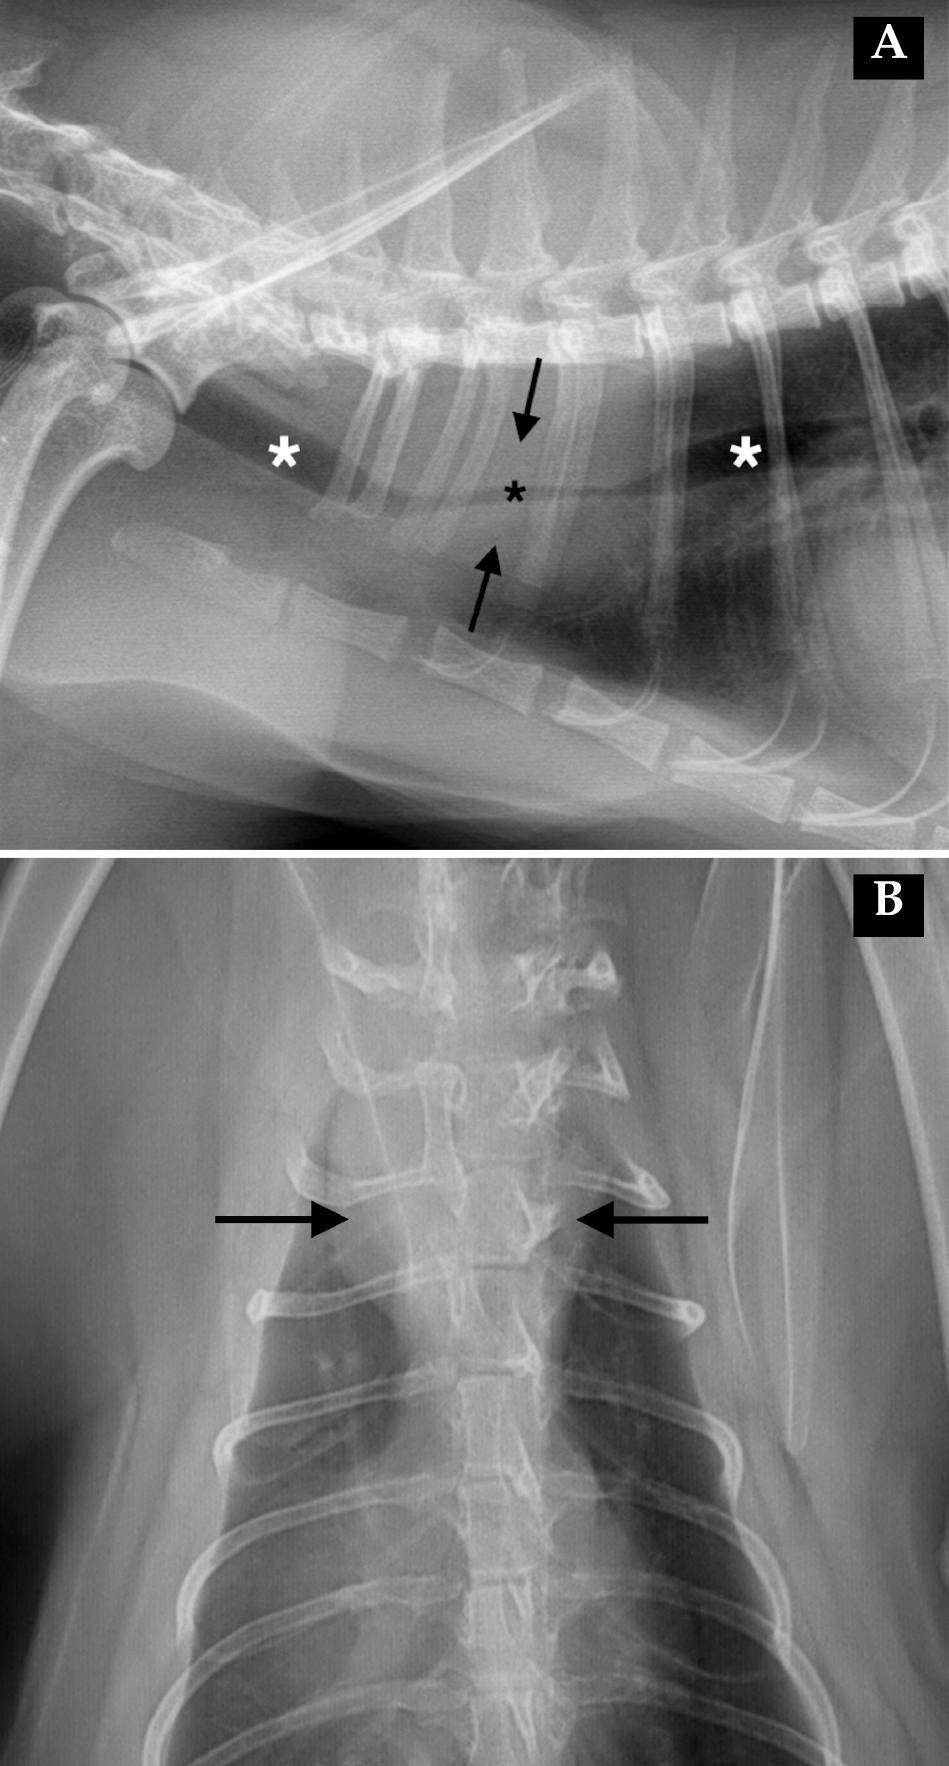

Se realizó un estudio radiográfico del tórax en proyecciones lateral derecha y dorsoventral (Fig. 1).

Radiografías de tórax de una gata hembra de 4 años. (A) Proyección lateral derecha. (B) Proyección dorsoventral.

Ambas proyecciones mostraron la presencia de una masa de opacidad tejido blando-líquido localizada a nivel del mediastino craneodorsal a la altura de los espacios intercostales 1 a 3 (Fig. 2). La lesión medía aproximadamente 30 mm de anchura x 38 mm de longitud y rodeaba concéntricamente la luz traqueal, produciendo una estenosis marcada y localizada de la estructura, con un diámetro reducido de 1,2-4,4 mm, en comparación con los 6 mm observados en el resto de la región cervical y torácica.

Imágenes ampliadas de las radiografías de la Figura 1. (A) Proyección lateral derecha. (B) Proyección dorsoventral. Se observa una masa de opacidad tejido blando-líquido (flechas negras) afectando a la porción torácica de la tráquea. La masa se extiende a la altura del segmento vertebral T1-T3, causando una reducción significativa de la luz traqueal (asterisco negro) en comparación con el diámetro normal de la tráquea (asteriscos blancos).